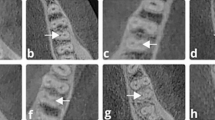

Different CSRCs and RGs in mandibular molars were presented in (Fig. 5).